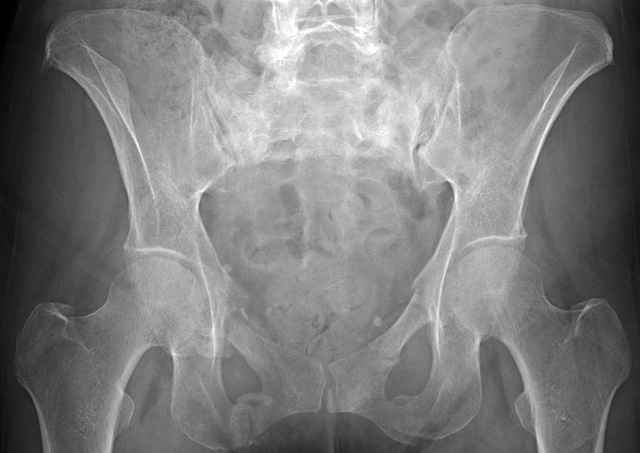

I’ve operated on 30-35 similar symptomatic patients... usually females in that same age range and most with prior trauma and then with sustained chronic activity related pain due to presumed insufficient healing and resultant ring instability (enough to hurt but not displace too much)...almost all have xray evidence of most of us would consider “hypertrophic” ramus nonunions, and most all have some form of sacral or other posterior ring corresponding injury.

If you examine them for mechanical ring instability, you’ll feel them collapse in your hands as you do... most are overweight to fat to downright obese so the mechanical examination can be a real challenge, but when you anesthetize them you can repeat it under fluoroscopy and see the ramus collapse and displace.

Here are a recent patient’s example slides...

54 yo Female Fell c/o Pain

Initial Films

?Instability on Exam - Limited by Pain

NonOp Initial Mgmt

3 Months After Fall

Continued Pain & Immobility

(+) Instability to Compressive Manual Exam

Pelvic CT Scan - 3 Months After Fall

Sacral Injuries

Ramus Fractures

Percutaneous Fixation

(B) Ramus-Retrograde

2 TransIliac-TransSacral

Upper Segment